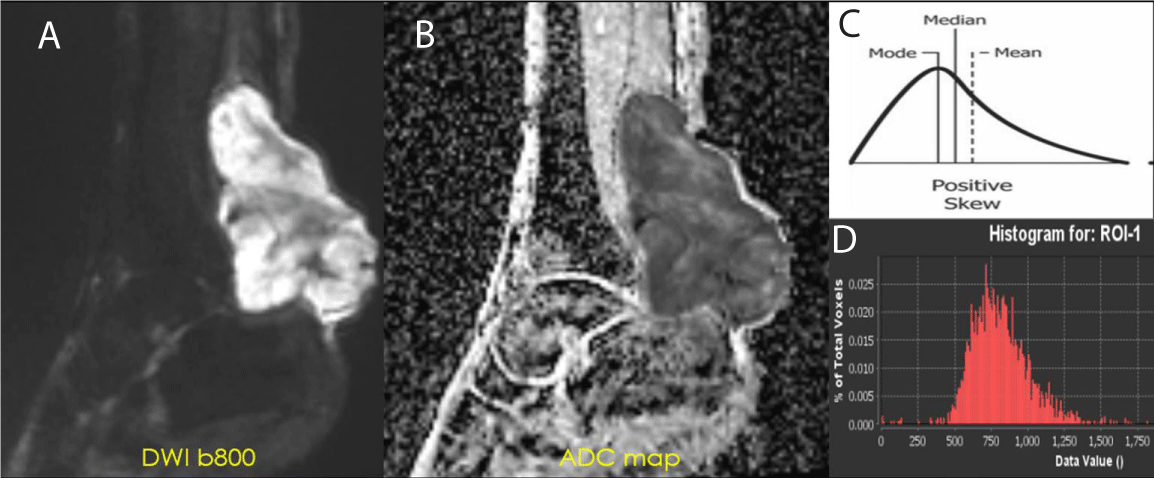

During treatment for sarcoma, hemorrhage patterns can appear on SWI. These patterns include “interstitial,” “globular,” “luminal,” and incomplete and complete “peripheral ring-like” tumor wall hemosiderin impregnation. If bleeding occurs, it is typically associated with low SWI-mean values and a left-sided intensity histogram with positive Skewness. Our experience has shown that a complete T2* hypointense ring is a typical SWI morphologic pattern observed in the good responder group [21-24] (Figure 4). The CE-SWI sequence provides additional and valuable information and typically adds no more than an additional 4-5 minutes to the MRI exam. As a result, it has become a structural sequence of our routine extremity tumor MRI protocol [25,26].

Figure 4: SWI: Hemorrhage as a Biomarker of Response. SWI of right thigh demonstrating an undifferentiated pleomorphic sarcoma (UPS) at different stages during therapy (A-Baseline, B-Post-chemo initial, C-post chemo final, D-Post-radiation). 99% necrosis on the histologic specimen.